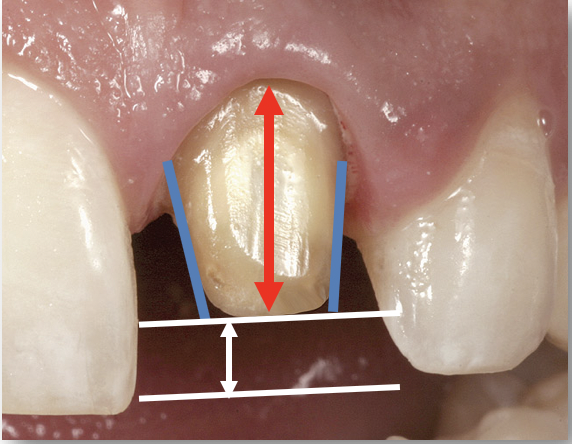

The most important factors to consider in preparing teeth for single-unit restorations are the taper (convergence), height (clinical crown height-how much tooth structure is above the gingiva and the height of the preparation), and reduction (Figure 1).6 Less than or equal to 20 degrees of taper or convergence is clinically appropriate. Overly tapered preparations will prevent the final restoration from being retentive. A preparation that is modestly parallel, while still achieving a good draw, is optimal. A 4-mm crown height is minimally adequate. If the height of the preparation is less than 4 mm, additional retentive features should be considered, such as slots and grooves in the preparation.

Fig 1. The most important factors to consider in preparing teeth for single-unit restorations are the taper, height, and reduction.

Figure 1